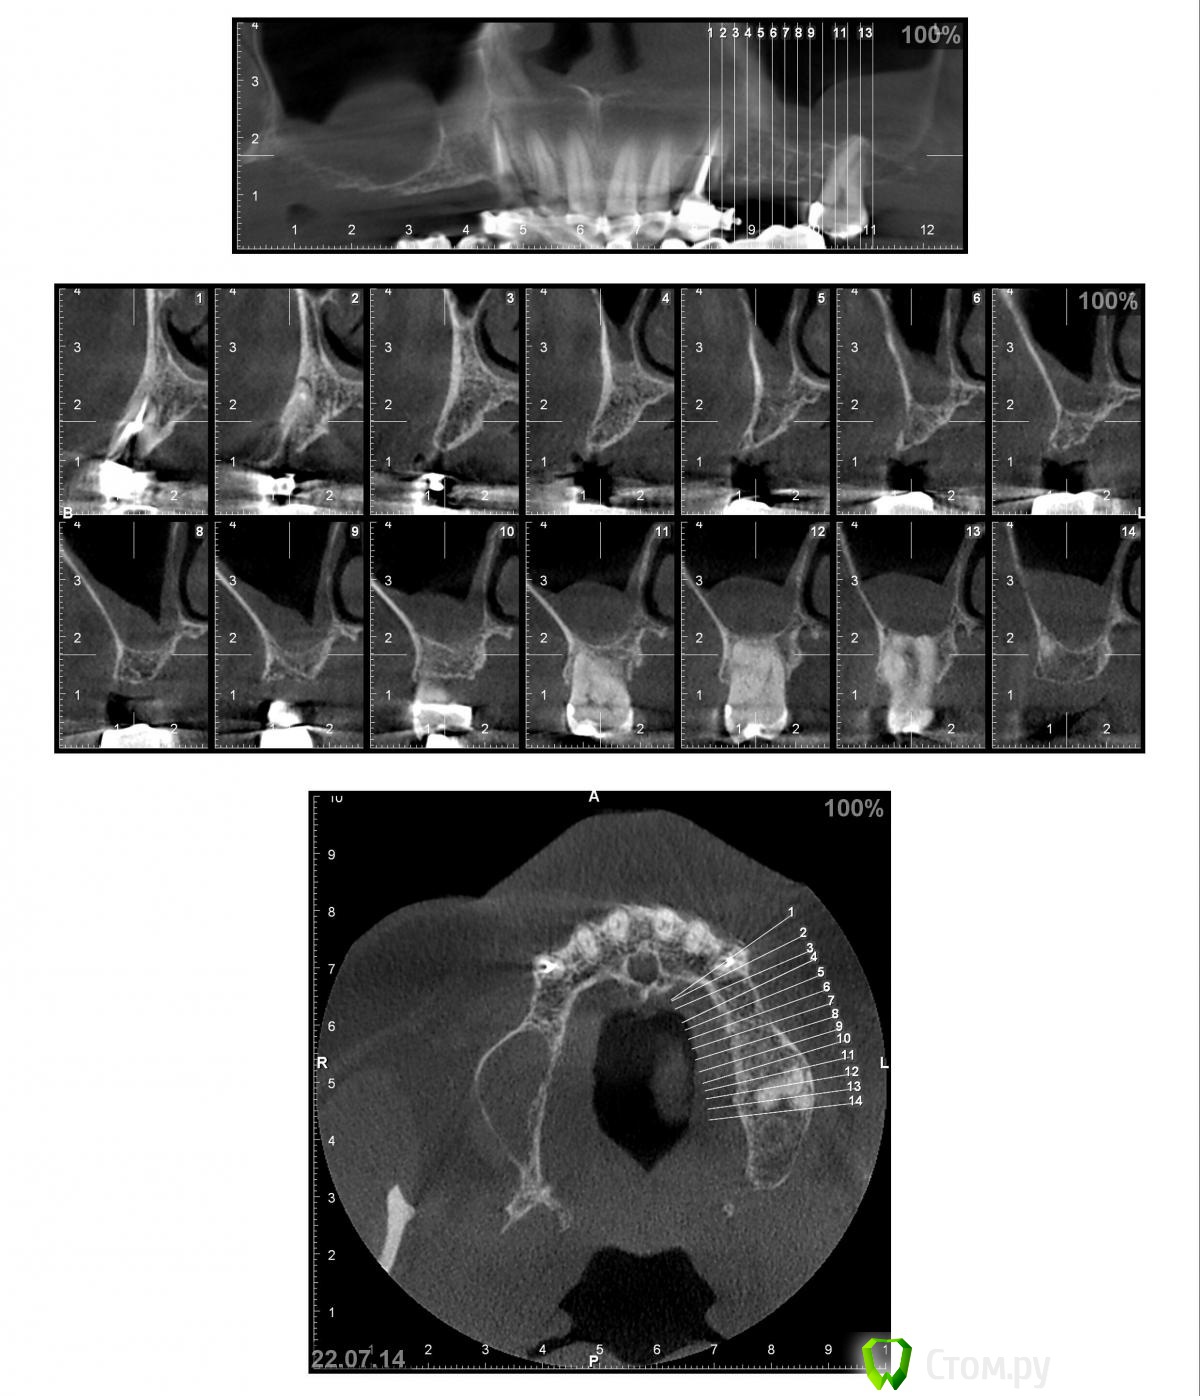

Nadeghda Опубликовано 13 октября, 2014 Поделиться Опубликовано 13 октября, 2014 Доброго времени суток, коллеги!Хотела узнать мнения относительно вариантов протезирования в/ч пациента.После консультации ЛОР - врача от оперативных вмешательств на ППН отказался. 13 и 23 удалены, лунки затягиваются. Варианты:1) имплантаты 13,15,23,25- мостовидные конструкции2) имплантаты 13.23; 15 и 25 - под углом 35'(ski)- локаторы- съемный протез3) имплантаты 13,23; 15,25- под углом 35' - мостовидные протезыМожет еще кто-нибудь что-либо предложит?Заранее спасибо! Ссылка на комментарий